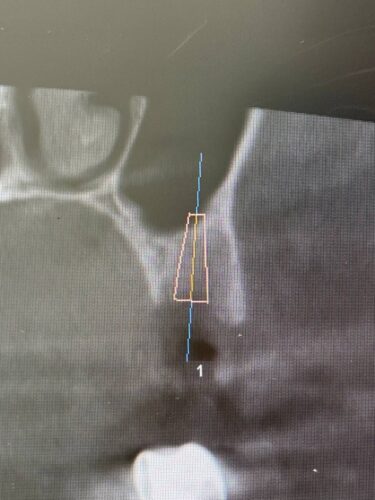

Установка импланта